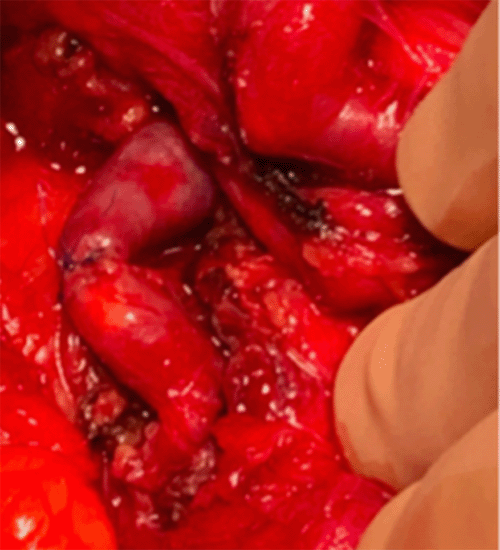

In a hybrid operative suite, access was obtained through the right common femoral artery under ultrasound guidance in a retrograde manner with 5F sheath placement. There was conversion to 6F RDC Destination Terumo sheath (Terumo Medical Corporation, Tokyo, Japan). An aortogram was initially performed in which celiac occlusion was observed directly off its origin. Then, selective SMA first-order arteriography was performed and revealed a calcified arterial segment of the SMA with inflow and outflow through the aneurysm. The outflow vessel then filled the GDA, hepatic, gastric and splenic vessels in a retrograde fashion, which was attributed to the celiac occlusion; the procedure was aborted due to these findings (Figure 2). As previously discussed, she was then admitted to the hospital for open preoperative planning. Vein mapping was completed before OR. An exploratory laparotomy was performed with mobilization of the duodenum to obtain proximal and distal control of the aneurysmal segment (Figure 3). The segment was excised, and an interposition bypass was performed utilizing the greater saphenous vein in an end-to-end fashion with 6-0 Prolene (Figure 4). Adequate flow was ensured distally with palpation and doppler signal. Her abdomen was closed in the usual fashion without drain placement. Final pathology reported a mesenteric arterial aneurysm, 3.5 × 2.5 × 2.4 cm overall, with moderate atherosclerosis and dystrophic calcification (Figure 5). The patient was discharged on postoperative day six. She had returned to work and daily activity without back pain by her two-week follow-up appointment.

Figure 3. Proximal and Distal Control Established. Published With Permission